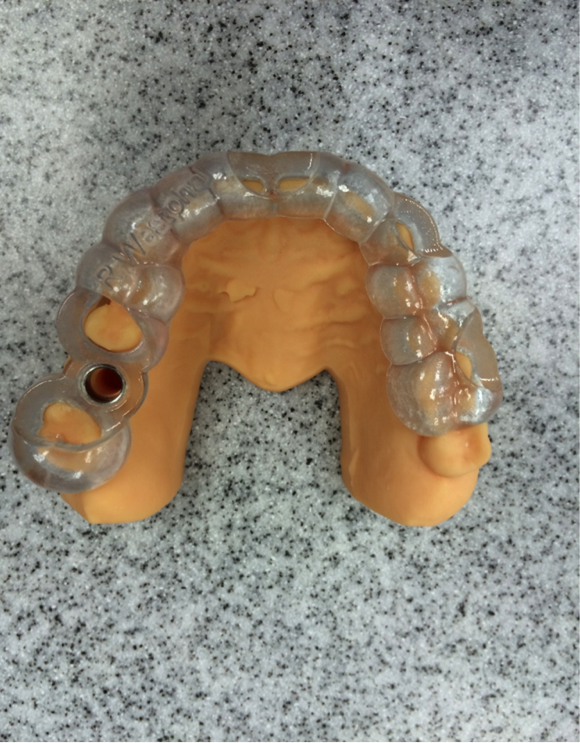

Fig 13. Diagnostic wax-up of tooth No. 3 restoration placed in model.

Figure 13

In this case, the patient’s right maxillary first molar had been extracted, and the site was grafted. The periapical radiograph taken after 6 months of healing indicated the presence of dense bone (Figure 11). There was also ample attached mucosa (Figure 12). Impressions were taken, a diagnostic cast was made, and a wax-up of the restoration was placed in the model (Figure 13). To make the radiographic guide for this case, a silicone putty index was created over the diagnostic wax-up, as described earlier. A panoramic radiograph and a CBCT scan (Figure 14) were taken with the radiographic guide in place; the guide post in the index can clearly be seen.